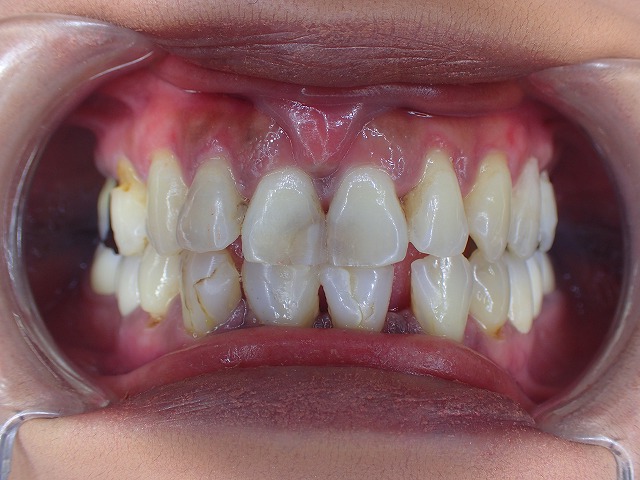

初診時画像 レジン充填 虫歯治療のあとが目立ちます レジン充填は劣化します

レジン充填が多数してあります。

この状態だと劣化して着色以外にも

大きく崩れてくるリスクがあります。

奥歯ないために、前歯で咬む癖があり

歯の先端から崩れ始めています。

下顎の前歯は2本欠損しています。